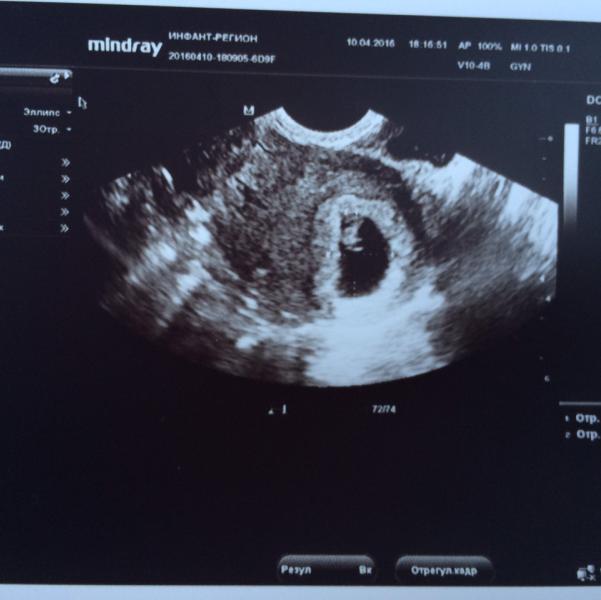

Сегодня в 18:00 сходила наконец-то на узи, сделали вагинальное. Плод на месте, такой кроха... 8-10 мм примерно. Я правда не знаю норма для такого срока или нет.

По поводу сердцебиения. Оно было четкое, равномерное и громкое, на экране пару раз я даже видела красную точечку внутри плода, было похоже на его сердечко. Но врач сказала, загадывать не будет, потому что это могло быть и мое сердце. НО!!! У меня аритмия, и мое сердце НИКОГДА так равномерно не билось, к тому же в момент прослушки сердца малыша я волновалась и мое сердце билось то очень быстро, то медленно и неравномерно. В на экране все было четко, и я это сказала врачу,мол это не мое сердце бьется. У малыша сердце билось 122 удара в минуту, мой пульс был около 100, но это опять же примерно. Плюс, небыло видно, что малыш шевелится 😔 может просто срок еще маленький или спал? Кто делал узи на таком сроке? Как четко было слышно сердцебиение вашего малыша? Шевелился ли он??